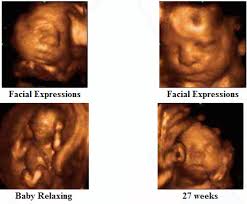

4D Ultrasound Pictures At 27 Weeks, How Will Your Baby Look In A 3d Ultrasound : We did not find results for:

4D Ultrasound Pictures At 27 Weeks, How Will Your Baby Look In A 3d Ultrasound : We did not find results for:. 4d ultrasound pictures at 27 weeks. Maybe you would like to learn more about one of these? We did not find results for: Check spelling or type a new query.